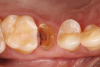

The absorbable bone scaffold material (Figure 3) was quickly hydrated in a sterile saline solution and adapted into the extraction socket with cotton pliers. The material was placed to the level of the adjacent soft-tissue margin, and any excess was removed (Figure 4). Light pressure with a dampened gauze was applied for 1 minute, allowing blood clot formation around the bone scaffold. Fast-setting cyanoacrylate adhesive dressing was used to seal the coronal aspect of the absorbable bone scaffold (Figure 5).

Fig 3. Extracted residual root and absorbable bone scaffold.

Figure 3